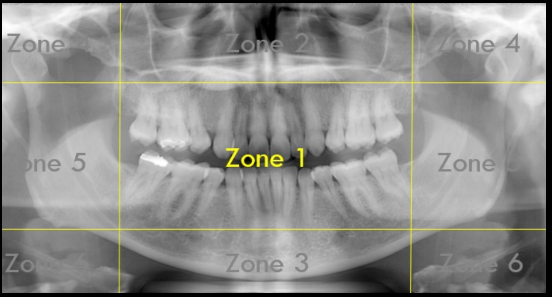

What Zone Is This?

Zone 1: Dentition